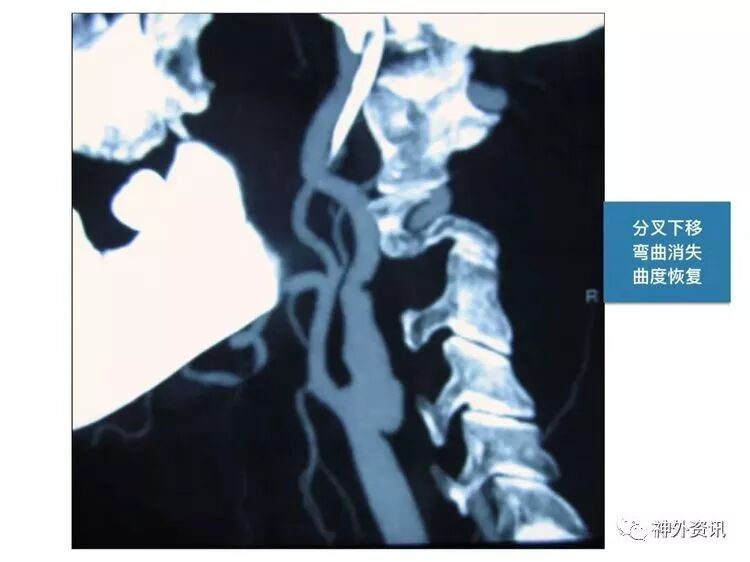

笔者的理解是:颈总动脉分叉部,位于下颌角水平以上(含下颌角水平)。此病例,颈内动脉狭窄部位,位于下颌角水平以上,接近颅底,属于高位CEA。

笔者认为,高位CEA手术的难点是:显露狭窄部位的远侧端(颅底侧方向)。